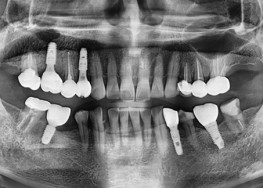

임플란트-치료-전후사진